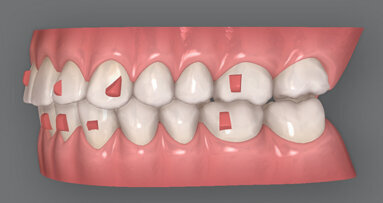

Dr. Luis Carriere: Jeho elegantní neinvazivní design umožnil revoluci v korekcích anomálií II. a III. třídy. Aparát se připevňuje pouze na tři zuby, proto je pohodlný a diskrétní, zároveň umožňuje použití progresivní filozofie „Sagittal First“ pro terapii anterio-posteriorních diskrepancí na začátku léčby, kdy pacienti spolupracují nejlépe. Působí jemnou, přirozenou silou, která pohybuje zuby, kontroluje jejich posuny a zajišťuje korekci skusu a vyrovnání zubů při přípravě na ošetření fixními nebo fóliovými ortodontickými aparáty. Aparát umožňuje zkrátit čas léčby ve smíšeném chrupu u dospívajících pacientů i u dospělých.

Korekce II. nebo III. třídy se uskutečňuje na začátku ortodontické léčby, dokud v ústech nepůsobí žádné soupeřící síly evokované zámky nebo jinými aparáty. Zároveň je to v době, kdy je pacient nejvíce motivovaný a jeho spolupráce je na nejvyšší úrovni. Dosažení I. třídy je jednoduché a obvykle je dokončeno za tři až čtyři měsíce. Použití Carriere Motion 3D aparátu řeší sagitální rozměr, čímž se sníží potřeba extrakcí nebo chirurgického zákroku. Napomáhá také repozici čelistí do lepšího vzájemného vztahu a vyrovnává poměry mezi nosem, rty a bradou kvůli dosažení harmonie tváře. Oba jsou biomimetické a mají gracilní jednodílnou konstrukci. To nabízí pacientům značnou svobodu při pohybu a výrazně vyšší komfort než při nasazení konvenčních anterio-posteriorních korektorů.

Dr. John Graham: Filozofie „Sagittal First“ s využitím Carriere Motion 3D aparátu je skutečným posunem v zažitém způsobu ortodontické léčby pacientů. Pomáhá mi zkrátit délku terapie – někdy až o jeden rok. Je velmi obohacující nabízet tento koncept léčby, protože pacienti, zvláště dospělí, už nemají pochybnosti, že léčba úspěšně postupuje vpřed. Vysvětlím jim, že se nezavazují ke dvouletému nošení fixních aparátů – s největší pravděpodobností to bude rok nebo méně.

Ortodontista i pacient se nemusí rozhodovat mezi fixními aparáty nebo alignery předtím, než je léčba zahájena. Je možné o tom přemýšlet, zatímco je korigován anterio-posteriorní vztah. Díky této nové metodě léčby mohu léčit více případů pomocí fóliových aparátů. Carriere Motion 3D aparát mi umožňuje snadno přeměnit složité pacienty s II. třídou na pacienty I. třídy; předtím by tyto složité případy pro léčbu alignery nebyly vhodné. Použití těchto aparátů mi také umožňuje zlepšit spolupráci pacientů. Když je kontrolujete během korekce zado-předního vztahu, můžete zjistit, jestli je pro ně léčba alignery vhodná.